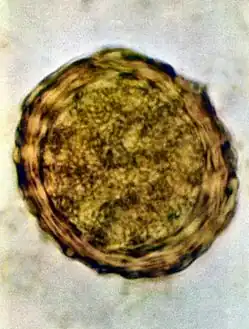

- Fertile egg as can be seen in a microscope

- Infertile egg

Ascaris lumbricoides is characterized by its great size. Males are 2–4 mm (0.08–0.2 in) in diameter and 15–31 cm (5.9–12 in) long. The male's posterior end is curved ventrally and has a bluntly pointed tail. Females are 3–6 mm (0.1–0.2 in) wide and 20–49 cm (7.9–19 in) long. The vulva is located in the anterior end and accounts for about one-third of its body length. Uteri may contain up to 27 million eggs at a time, with 200,000 being laid per day. Fertilized eggs are oval to round in shape and are 45–75 μm (0.0018–0.0030 in) long and 35–50 μm (0.0014–0.0020 in) wide with a thick outer shell. Unfertilized eggs measure 88–94 μm (0.0035–0.0037 in) long and 44 μm (0.0017 in) wide.[9]